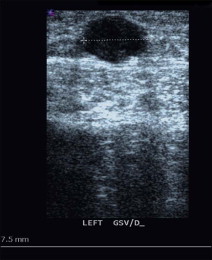

The great saphenous vein (GSV) is imaged with the patient facing the technologist and the study leg slightly forward and externally rotated. The vein is examined for dilation, compressibility, and echogenicity in the transverse orientation. The longitudinal view is also assessed, and thickness of the vein wall, valvular changes or any echogenicity are documented ( Figs 10.1–10.5 ). The operator tests for reflux in the axial vein and perforating veins using color flow, and also uses the pulsed Doppler with the probe in longitudinal orientation to test for reflux in the saphenofemoral junction, the common femoral vein above and below the saphenofemoral junction, and the proximal GSV. The Valsalva maneuver is appropriate for provoking reflux in the groin, but may not provoke reflux inferior to the groin if there is a competent valve in the groin area. Therefore, compression of the leg above and below the segment being interrogated is used to detect evidence of reflux in the target segment. For example, saphenofemoral and proximal great saphenous reflux may be masked during the Valsalva maneuver by the presence of a competent valve in the proximal common femoral vein. The author tests for this by squeezing the upper thigh between two hands (lateral and medial) while interrogating the proximal GSV with pulsed Doppler and looking for ‘to and fro’ flow. The Valsalva maneuver may also fail to demonstrate reflux in the more inferior segment of the GSV and the practitioner must depend on proximal and distal compression maneuvers to elicit reflux when it is significantly inferior to the saphenofemoral junction.

Some surgeons use thresholds of ≥6 mm in diameter with reflux of at least 0.5 seconds in duration when considering ablation or removal of the axial GSV. However, the ideal patient for classic stripping of the GSV will have: (1) a dilated GSV (≥8 mm in diameter adjacent to the saphenofemoral junction) with saphenofemoral or proximal great saphenous reflux lasting at least 1.5 seconds; (2) clusters of varicose branches in the calf and/or thigh; (3) absence of significant perforating vein reflux; and (4) no evidence of significant changes of deep vein thrombosis (DVT). Removal may still be indicated in certain patients with distal communicating branches off a normal-caliber GSV with reflux, or with dilatation of the GSV without observable reflux. In practice, most patients with symptomatic varicose veins disease have areas of the GSV much larger than 8 mm in diameter and reflux lasting much longer than 1.5 seconds. The location of the lowest connecting perforator, which is often in the distal thigh or very proximal calf, is marked during the duplex examination since removal of the vein below this level is unnecessary and increases the chance of saphenous nerve injury ( Fig. 10.7 ). In practice, it is rarely necessary to remove the GSV below the upper calf as is discussed in more detail below.